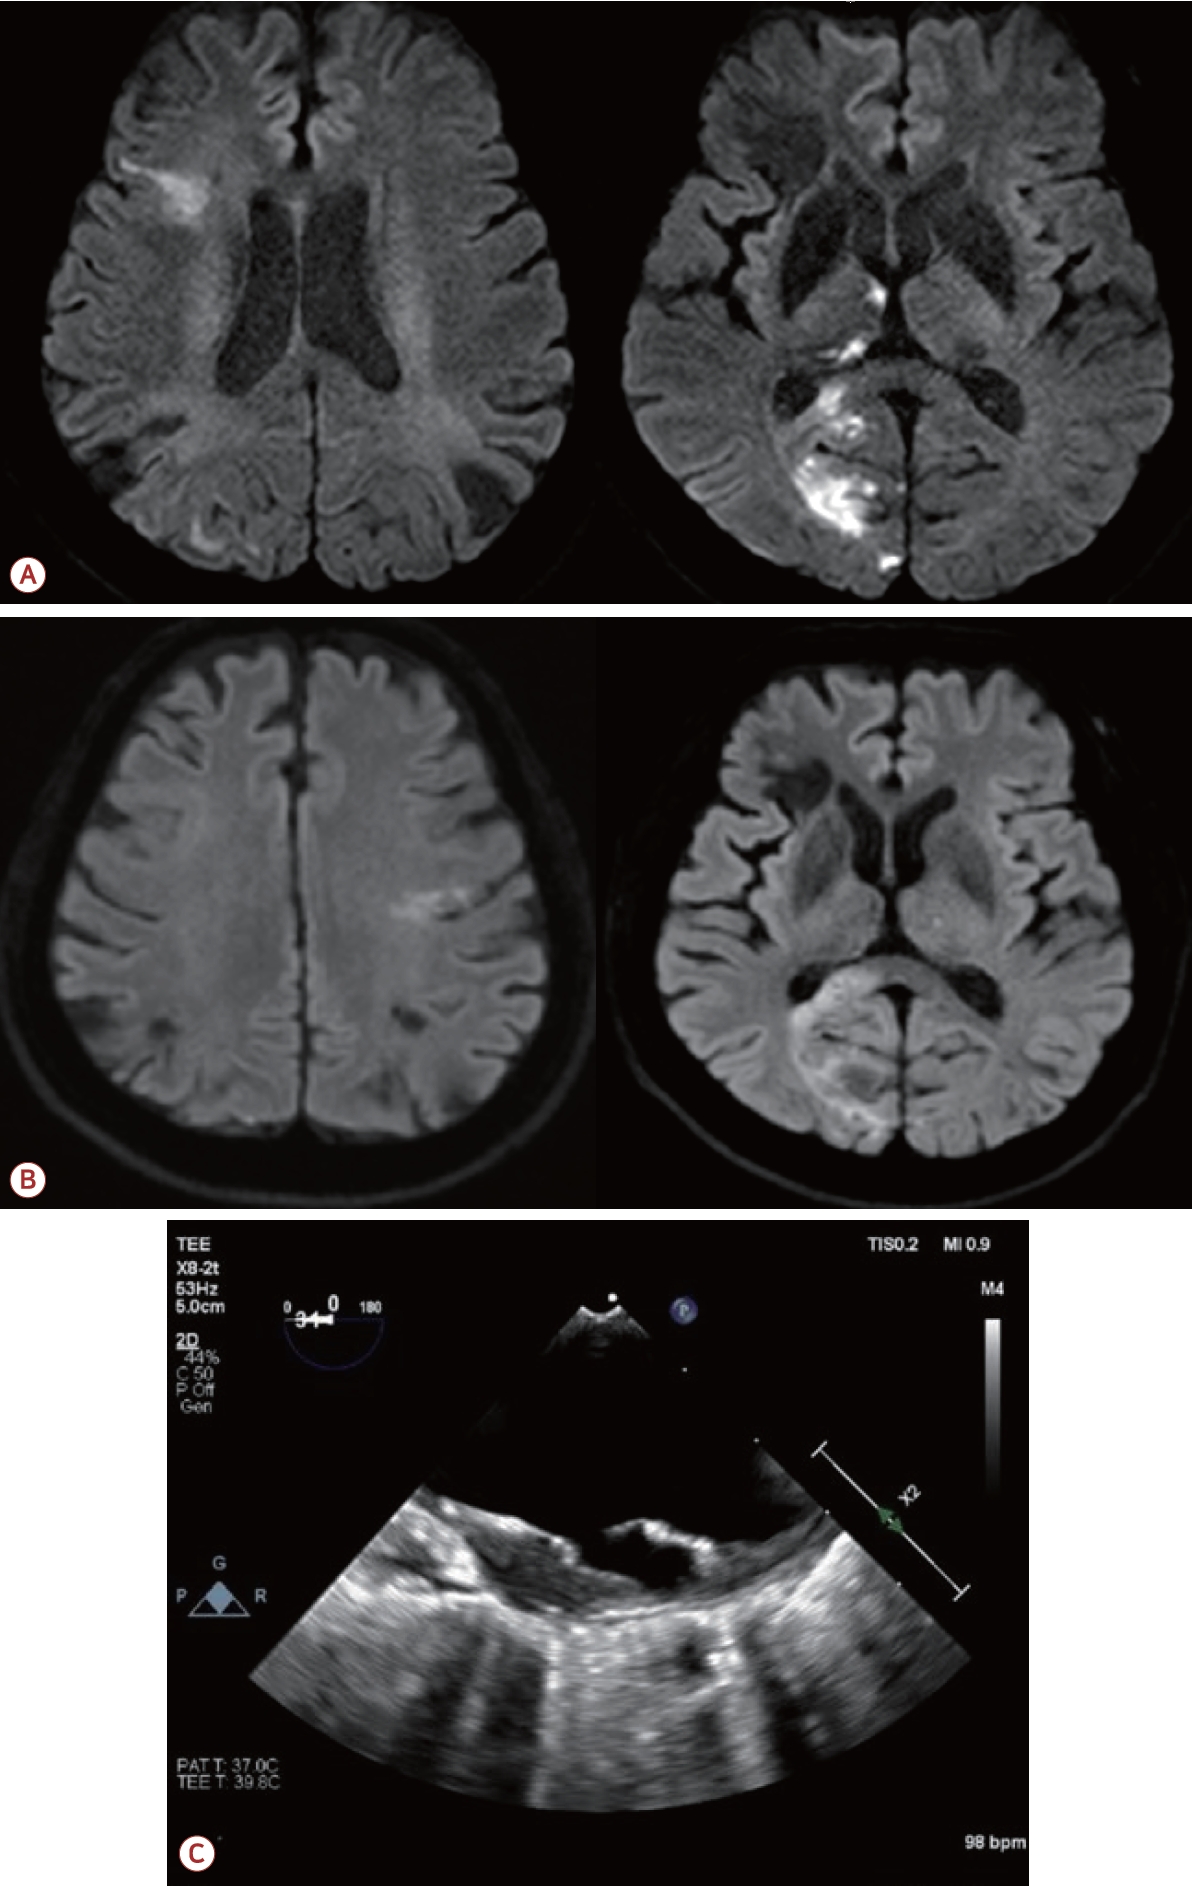

73세 남자가 최근 3개월간 반복적인 허혈뇌졸중으로 내원하였다. 환자는 고혈압, 당뇨, 안정협심증의 기저 질환을 가지고 있었다. 초기 뇌자기공명영상(magnetic resonance [MR] imaging)에서 좌측 대뇌반구와 우측 소뇌에 다발성 허혈 병변이 관찰되었으며(Fig. 1-A) 혈관 검사에서는 좌측 내경동맥근위부(internal carotid artery, ICA)에 76.7%의 협착(NASCET 기준)이 확인되었고 동시에 보바인형 대동맥궁(bovine arch, 공통 기시형 변이)이 관찰되었다(Fig. 1-B). 이에 따라 증상성 중증도 이상의 ICA 협착으로 판단하여 좌측 CEA와 이중 항혈소판 요법이 시행되었다. 그러나 시술 2개월 후에 우측 후 대뇌동맥(posterior cerebral artery, PCA)과 우측 중대뇌동맥(middle cerebral artery, MCA) 영역에 재발성 뇌경색이 발생하였고(Fig. 2-A) 한 달 후에는 좌측 MCA와 PCA 영역에 새로운 뇌경색이 재발하였다(Fig. 2-B). 기존에 진행되었던 두개경유도플러 검사에서 심방중격 결손이나 미세색전 신호를 시사하는 소견은 확인되지 않았고 흉부경유심초음파에서 좌심실 박출률은 정상 범위었으며 3일의 홀터 모니터링에서도 심방세동은 관찰되지 않아 심장성 색전은 배제하였다. 반복되는 색전성 병변의 원인을 찾기 위하여 식도유심초음파(transesophageal echocardiography, TEE)가 진행되었으며 대동맥궁 대만부(greater curvature)에 위치한 7 mm 크기의 궤양성(ulcerated), 유동성(mobile)의 고위험 죽경화판(high-risk aortic arch plaque)이 관찰되었다(Fig. 2-C). 추가적인 머리 혈관조영에서는 기존에 확인되었던 좌측 경동맥의 중증도 협착은 호전 상태를 보였으며 보바인형 대동맥궁 및 팔머리동맥에 동맥류성 확장(aneurysmal dilatation)을 확인할 수 있었다(Fig. 3-A). 이에 신경과, 순환기내과, 영상의학과, 심장혈관흉부외과가 포함된 다학제 협의를 통해 단계적 하이브리드 치료가 결정되었다. 첫 번째 단계로 부분 디브랜칭 수술(좌쇄골하-좌총경동맥우회술[partial debranching surgery, left subclavian-left common carotid artery bypass])이 시행되었다. 수술 한 달 후에 팔머리동맥에 스텐트이식편(endovascular brachiocephalic stent-graft)을 삽입하여 팔머리동맥류의 병적 분절을 제거하였다(Fig. 3-B, C). 스텐트 시술 이후 약 1년 6개월이 지난 현재까지도 환자는 지속적으로 이중항혈소판 요법을 유지하면서 추가적인 허혈 사건 없이 안정적으로 추적 관찰 중이다.